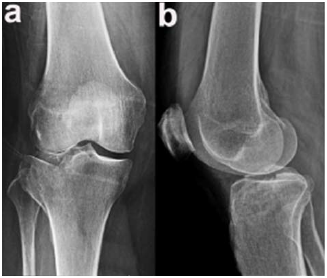

Um paciente de 39 anos de idade, vítima de queda de bicicleta, sofreu trauma no joelho direito. Foi levado ao pronto-socorro do hospital mais próximo, onde foram realizadas as radiografias apresentadas.

De acordo com Schatzker, é possível classificar essa fratura como do grupo